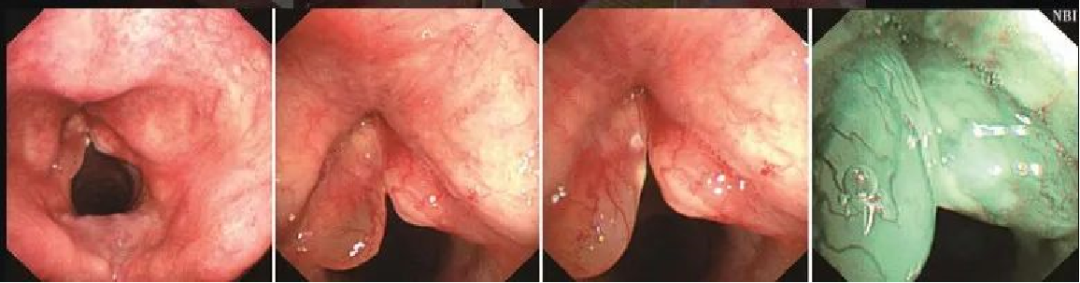

喉部早期癌

为什么喉镜后做活检电子鼻咽喉镜,让鼻、咽、喉部疾病无处可藏——2021橙乡微创论坛精彩速递(五)_https://www.jmylbn.com_新闻资讯_第15张

喉部结构基本完整,会厌及左、右披裂黏膜基本光滑,普通光下很难发现声带病变。NBI模式下可见IPCL扩张形成典型的斑点状表现。病变累及左侧声带近全长,向前累及并跨越前联合,侵达右侧声带前端约1/3。